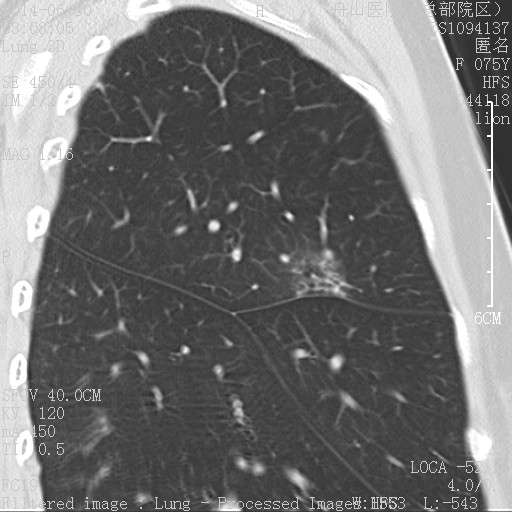

第三例曲霉菌:

3rd 在隔离肺的支气管里 也是在扩张的支气管内,有炎症细胞 紫红的可能是锰铁化,曲霉菌能吸收空气中的锰铁元素,在周边